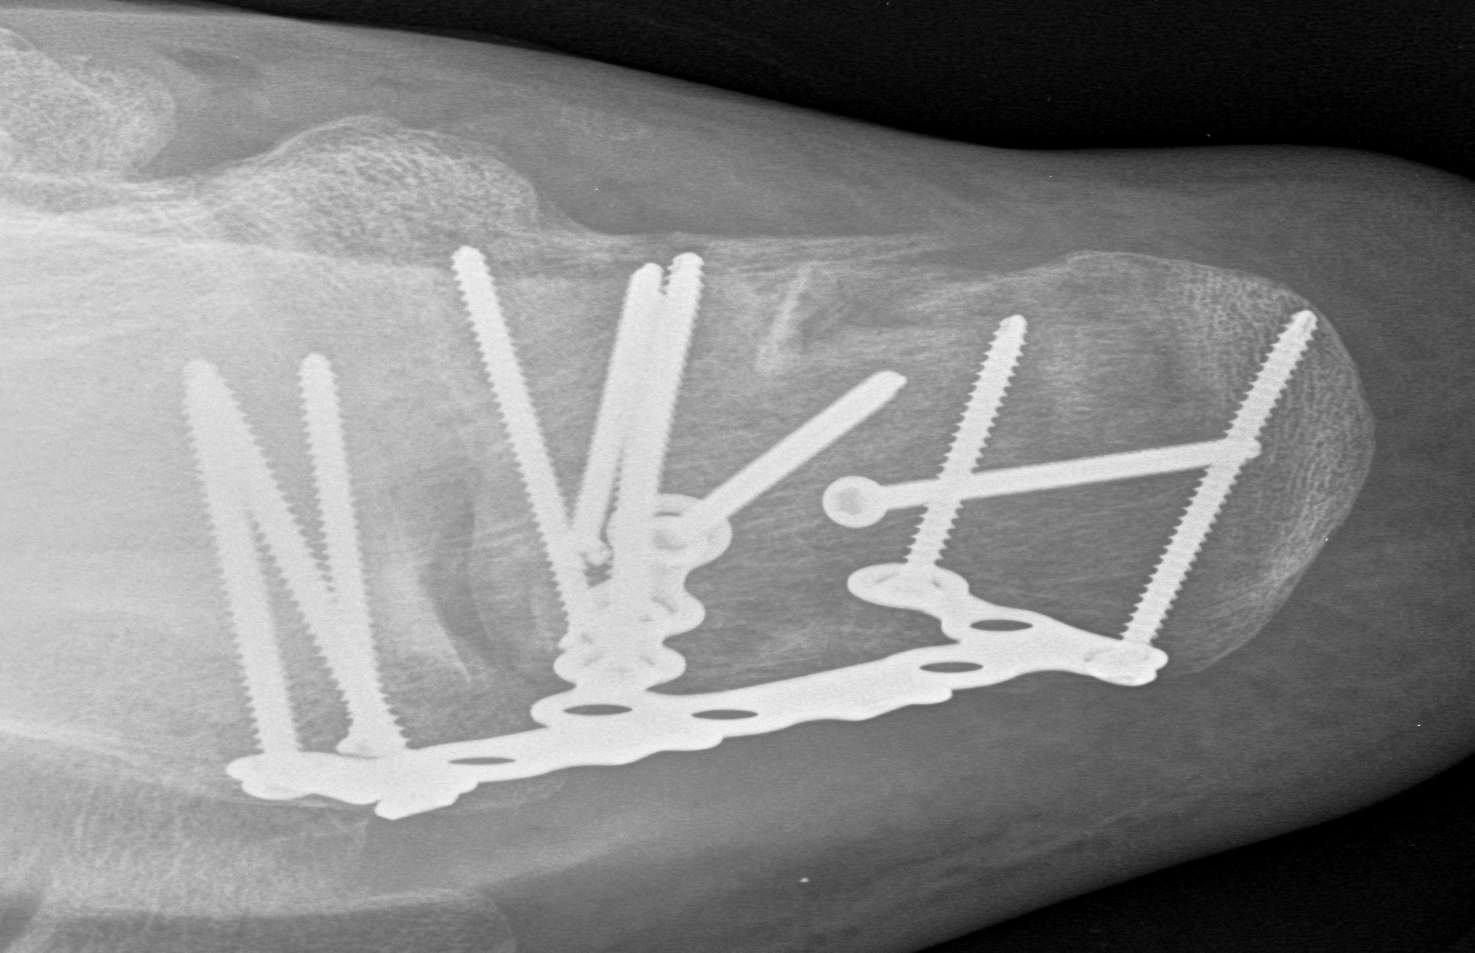

ORIF lateral plate using extensile lateral approach

Depuy Synthes calcaneal locking plates PDF

Anatomical contoured locking plate